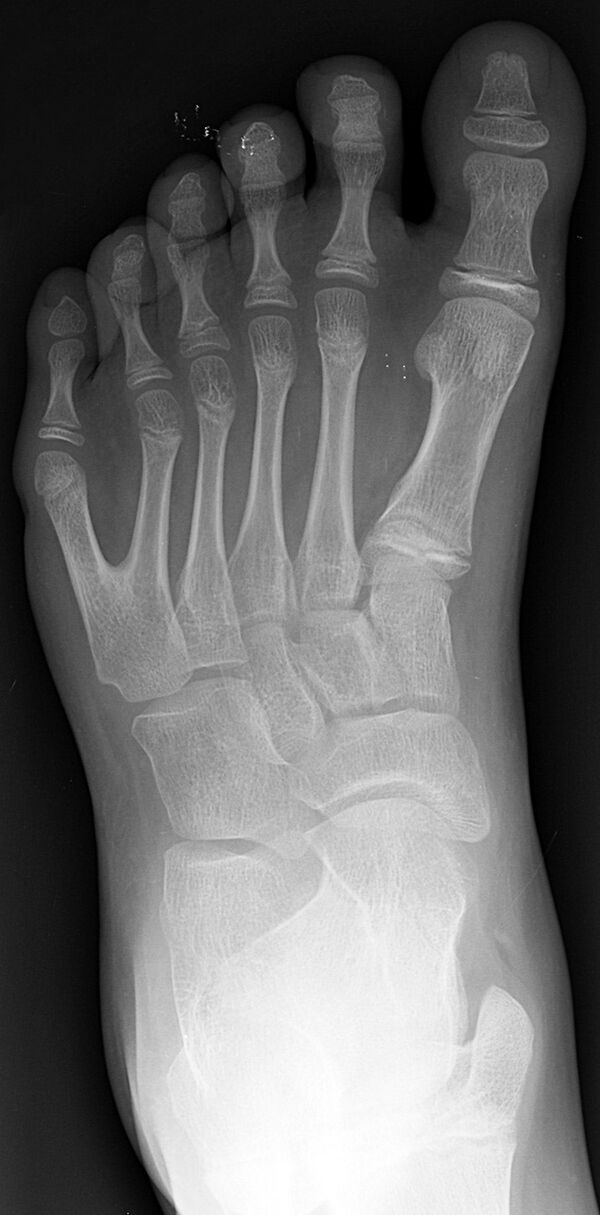

Полидактили́я (др.-греч. πολύς — много + δάκτυλος — палец, синоним — многопалость), также известная как гипердактилия — порок развития, характеризующейся бо́льшим, чем в норме, количеством пальцев на руках или ногах у человека, собак, котов и лошадей. Противоположным отклонением является олигодактилия.

У людей и животных она может проявляться как на одной, так и на обеих руках. Обычно дополнительный палец представляет собой небольшой кусочек мягкой ткани, которую можно удалить. Иногда это просто кость без суставов; очень редко лишний палец бывает полноценным. Дополнительный палец чаще всего образуется со стороны мизинца, реже на стороне большого пальца и очень редко между средними пальцами. Обычно лишний палец является аномальным разветвлением обычного пальца, редко возникает на запястье, как обычный палец.